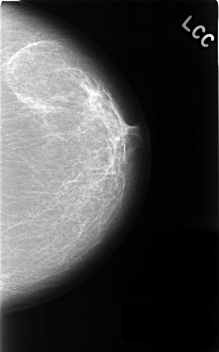

C_0370_1.LEFT_CC

LEFT_CC LINES 4568 PIXELS_PER_LINE 2840 BITS_PER_PIXEL 12 RESOLUTION 50 NON_OVERLAY